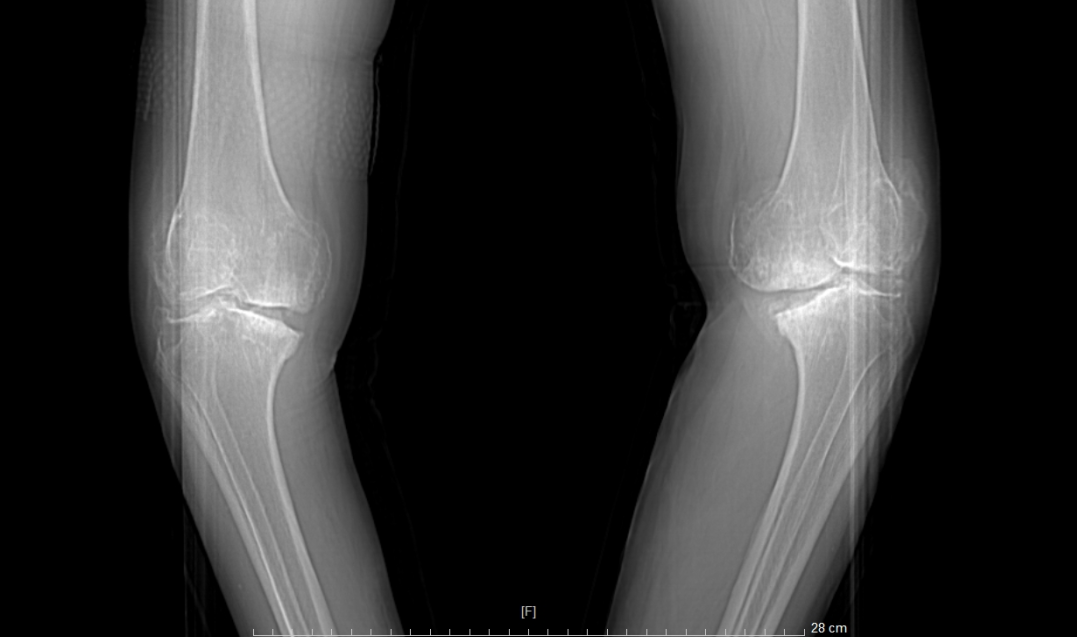

患者术前VS术后对比

关节置换术仅适用于关节软骨严重(或完全)磨损的病人,须严格掌握适应证-终末期膝骨关节炎、类风湿性关节炎、痛风性关节炎、创伤性关节炎、膝关节软骨坏死性疾病等。且须同时满足以下三个条件:

①站立位X光片中显示关节间隙消失或极度狭窄